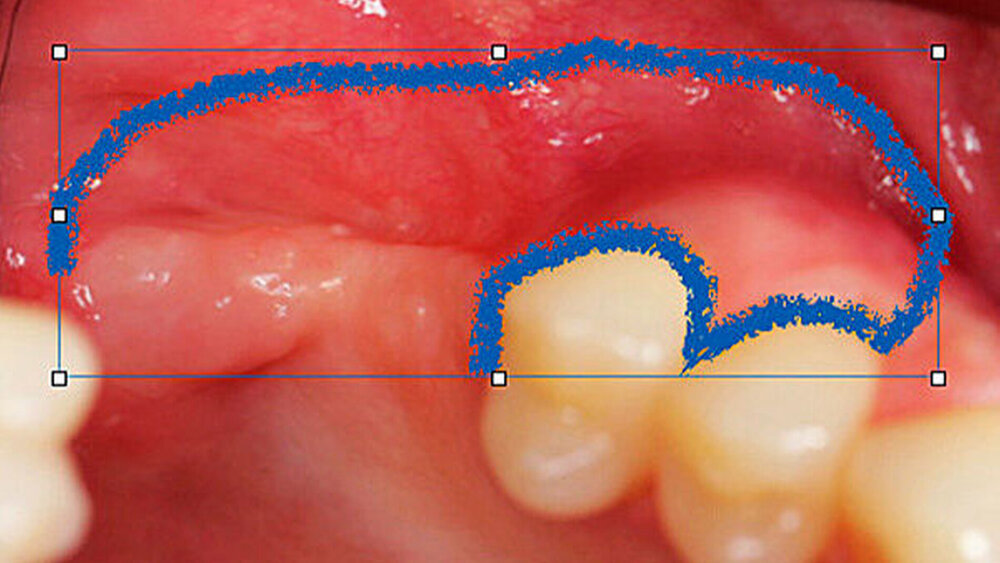

Ein 29-jähriger Patient stellte sich mit einer massiven Alveolarkammatrophie im rechten Unterkiefer in unserer Praxis vor. Diese lag in langen Jahren der Zahnlosigkeit begründet. Eine Beckenkammaugmentation kam für den Patienten nicht in Betracht. Dennoch wünschte er die Versorgung mit festsitzendem Zahnersatz. Nach ausführlicher Beratung entschied sich auch dieser Patient für eine Augmentation mit einem patientenindividualisierten allogenen CAD/CAM-gefertigten Knochenblock. Die DICOM-Daten des Unterkiefer-DVTs wurde an die Firma Zimmer gesendet, und es erfolgten wie im oben beschriebenen Fall eine virtuelle Planung und das virtuelle Design des allogenen Knochenblocks anhand der geplanten Implantatpositionen. Nach der üblichen Kontrolle und Freigabe des Chirurgen erfolgte die eigentliche Fertigung und Übersendung des Knochenblocks in die Praxis. Die Augmentation erfolgte auch in diesem Fall in Vollnarkose unter antibiotischer Abschirmung perioperativ mit Ampicillin. Die Schnittführung im Unterkiefer unterscheidet sich von der Sockelschnittführung im Oberkiefer aufgrund der Anatomie (N. mentalis). Auch bei diesem Patienten wurde eine tief im Vestibulum liegende bogenförmige Inzi‧sion durchgeführt, jedoch ohne die vertikalen Entlastungen. Nach streng subperiostaler Präparation erfolgte die Darstellung des N. mentalis. Die Vorbereitung des Spenderbetts sowie die Wässerung, Einpassung und Befestigung des allogenen Knochenblocks gestalteten sich wie im Fallbeispiel 1. Die Heilzeit des Knochenblocks dauerte ebenfalls sechs Monate. Zwei Implantate (Straumann) wurden nach krestaler Schnittführung in Lokalanästhesie eingebracht und heilten subgingival binnen drei Monaten ein. Aufgrund des massiven Volumenzuwachses war auch ebenfalls eine Vestibulumplastik im Zuge der Implantatfreilegung notwendig. Das Prozedere verlief ebenfalls wie im Fallbeispiel 1. Das freiliegende Gewebe wurde mit einer Kollagenmatrix abgedeckt. Dadurch konnte die Breite der befestigten Gingiva deutlich verbreitert werden.